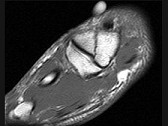

- 单项选择题女,25岁, 扭伤后足中部痛,结合图像, 最可能的诊断是 ( )

A、內侧楔状骨骨折

B、外侧楔状骨骨折

C、足舟骨骨折

D、中间楔状骨骨折

E、未见异常